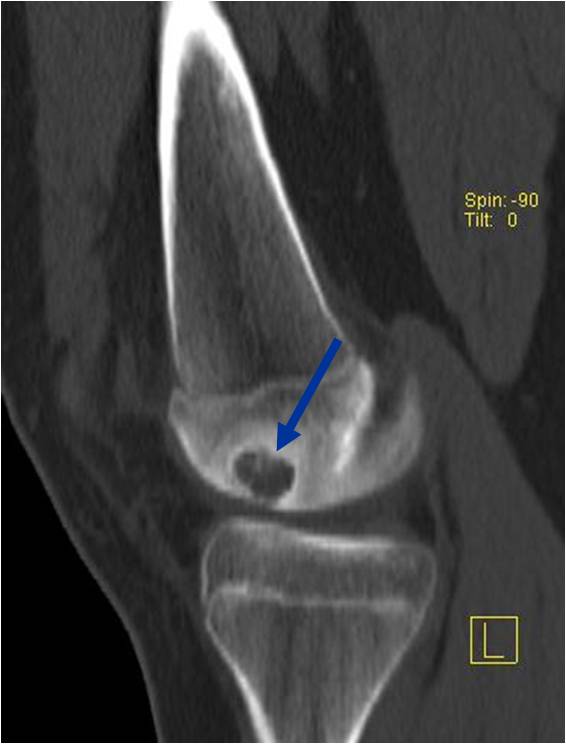

- Presents as a highly defined/well circumscribed geographic oval/round lytic defect

- Surrounded by rim of sclerotic bone

- Usually in epiphyseal region

- May have fine trabeculae and irregular calcifications

- Calcifications are often better detected with a CT scan but are not uniformly present

- (CT appearance)

- Most useful for detecting subtle mineralization not apparent on X-rays

- Useful for identifying intact periosteum around any expansile soft tissue component

- surrounding thin reactive shell of bone/mineralization (Egg Shell Rim of Calcification)

- helps place the tumor in a benign category

- extent of bone and cortical destruction

- whether the subchondral plate of bone adjacent to the articular cartilage has been destroyed or is intact